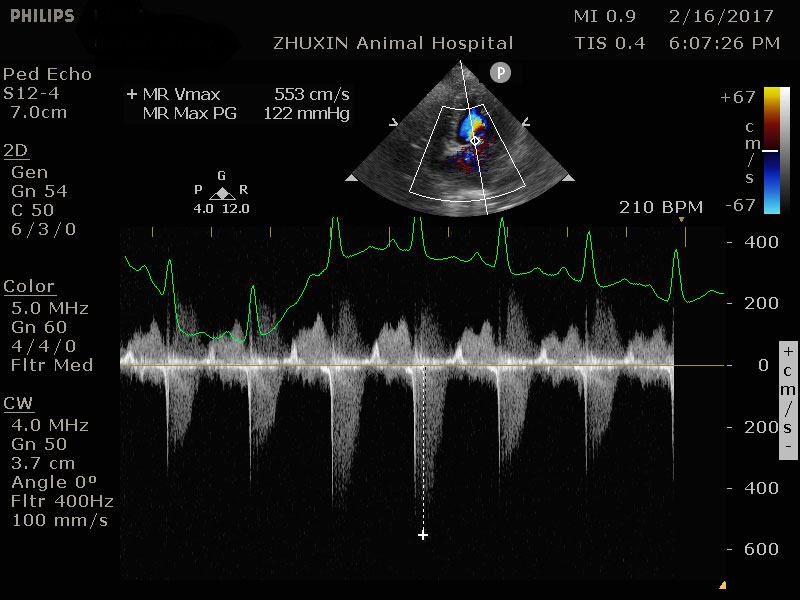

肥厚性心肌病導致血栓產生

美短右後肢突然疼痛拖行的貓咪經理學檢查懷疑為血栓造成,心臟超音波確診為肥厚性心肌病導致血栓產生,精確的診斷才有辦法良好控制疾病、保持生活品質、延長壽命。

心臟快速掃描結果

嚴重的左心房擴張

左心室壁明顯肥厚